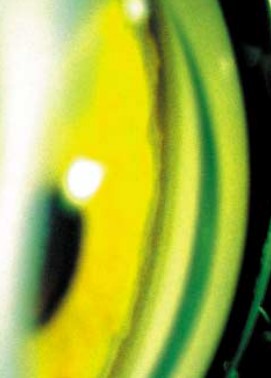

Эта своеобразная форма глаукомы встречается у лиц молодого возраста и характеризуется гипоплазией стромы радужек с обнажением ее пигментного эпителия. Уже при рождении ребенка отмечается наиболее яркий клинический признак заболевания — контрастная двухцветная окраска радужки. Процесс всегда двусторонний.

- Зрачковая зона радужки шире ресничной и выглядит как сероватое или желтое кольцо с ровной либо ватообразной поверхностью.

- Ресничная зона за счет обнажения пигментного листка имеет значительно более темный шоколадно-коричневый или сине-лиловый цвет.

- В прикорневой части ресничной зоны может отмечаться желтовато-оранжевого цвета недифференцированная губчатая мезодермальная ткань.

Левый глаз. Острота зрения OS=1,0. ВГД=18 мм рт.ст. Глаз спокоен. Роговица прозрачная. Имеется некоторая неравномерность ширины лимба, признаков заднего эмбриотоксона не отмечено. Передняя камера средней глубины, влага ее прозрачна. Радужка имеет двухцветную окраску, идентичную таковой правого глаза.